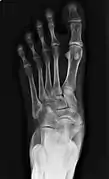

![]() X-ray of the foot showing an accessory navicular bone | |

An accessory navicular bone is an accessory bone of the foot that occasionally develops abnormally in front of the ankle towards the inside of the foot. This bone may be present in approximately 2-21% of the general population and is usually asymptomatic.[1][2][3] When it is symptomatic, surgery may be necessary.